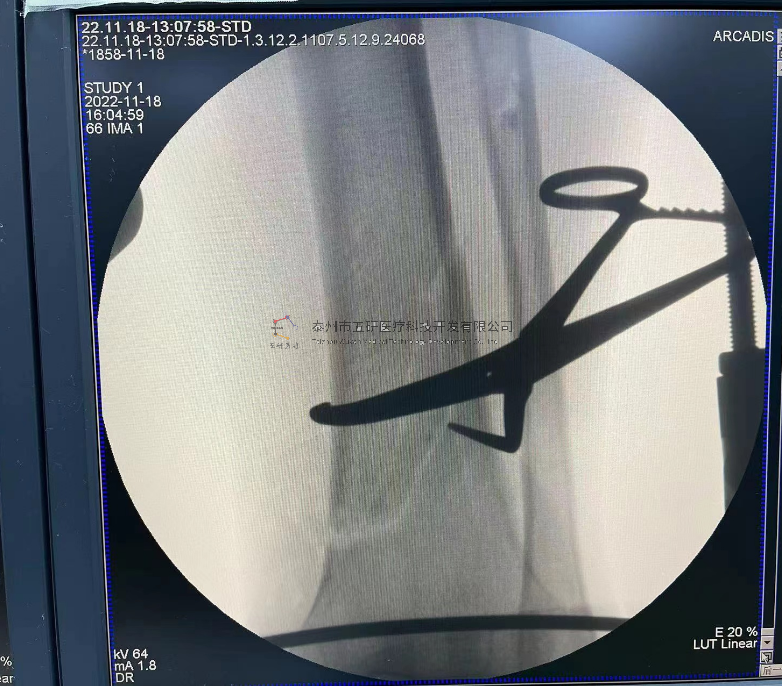

// 踝關(guān)節(jié)

本病例由中國中醫(yī)科學(xué)院望京醫(yī)院骨關(guān)二提供(術(shù)者:支架主任蔣主任)

【基本資料】患者,男,41歲

本病例踝關(guān)節(jié)骨折。手術(shù)名稱:左踝關(guān)節(jié)骨折外固定支架手術(shù)

【手術(shù)資料】